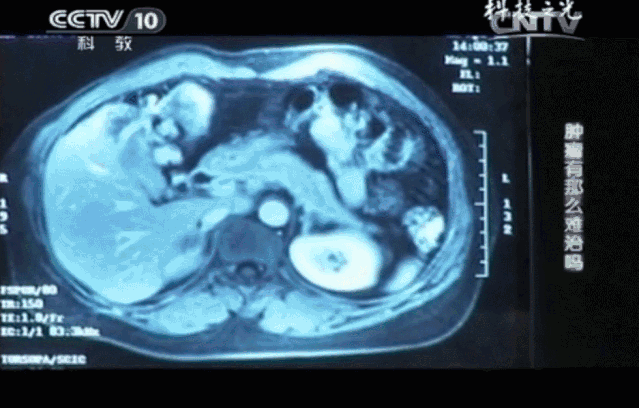

没过多久,噩耗再次传来。王女士的肝脏上出现了一个直径约为8cm的肝转移肿瘤,这让王女士彻底的绝望了。不愿再进行痛苦的治疗,王女士决定放弃治疗,与家人一起走完人生最后的半年时间。

不仅如此,连续4个月的CT结果对比分析,王女士的肝转移瘤从8公分缩小到2.5公分,肿瘤标记物指标回归正常,这些都说明肿瘤正在被免疫细胞一点点消灭。